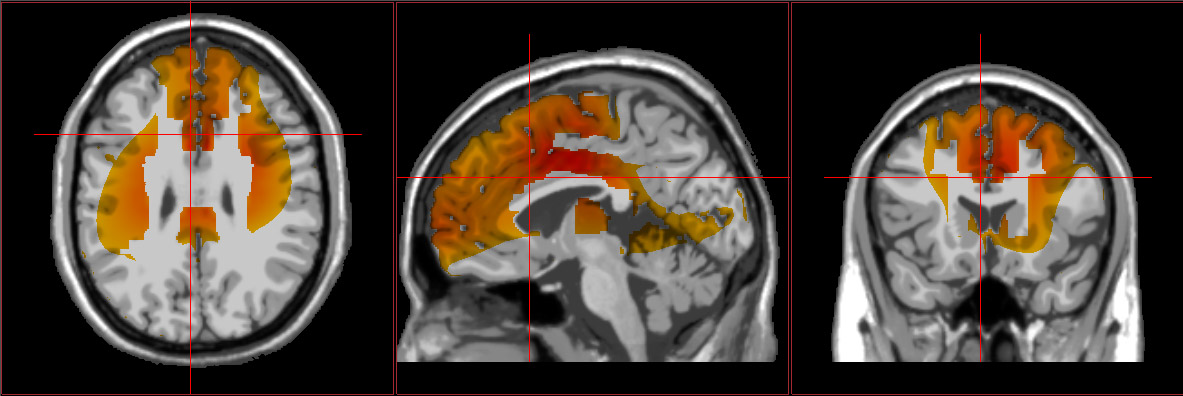

Source-localized electroencephalography (sLORETA) is a neuroimaging

technique that uses EEG data to localize the source of brain activity in specific

regions. It helps us understand the underlying neural roots of symptoms and

specific areas of dysfunction.

This neuroimaging can also assist with determining the most effective treatment

interventions, including which medications and/or supplements could be

beneficial, as well as neurotherapy protocols and other interventions designed to

improve functioning within regions showing impairment.